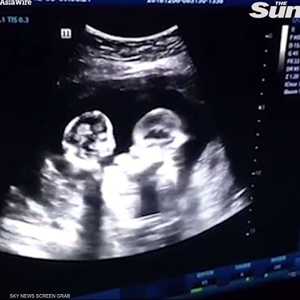

10:49 - 26 أبريل 2019بعد عام على زواجها، وهي في الثانية عشر من عمرها، أنجبت الأوغندية مريم ناباتانزي توأمين، وتبعهما 5 مجموعات من التوائم، ثم 4 مجموعات من التوائم الثلاثية، و5 مجموعات من التوائم الرباعية، ليصبح عدد أبنائها 38 ولدا وبنتا كلهم من التوائم.

ليس هذا فحسب، بل ذات مرة أنجبت مجموعة توائم سداسية، لكنهم ماتوا عقب الولادة وفقا لتقرير أعدته وكالة رويترز.

ووفقا لما تقوله مريم، وبعد أول حالة ولادة للتوائم، توجهت إلى الطبيب الذي أبلغها أن حجم مبيضيها كبيران بصورة غير عادية، ونصحها بعدم اللجوء إلى وسائل تحديد النسل عن طريق الأقراص بحجة أن ذلك سيتسبب لها بمشكلات صحية.